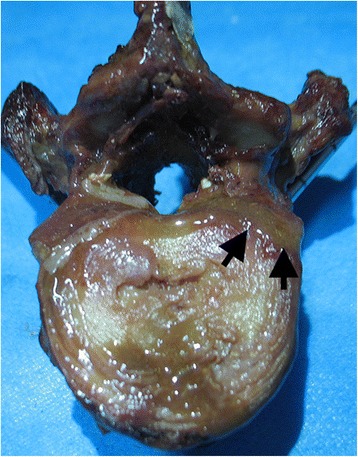

Figure 3.

Photograph of a vertebra without void creation after cement injection. The bone marrow (black arrows) was shown to be displaced out of vertebral body through defects in the cortical shell.